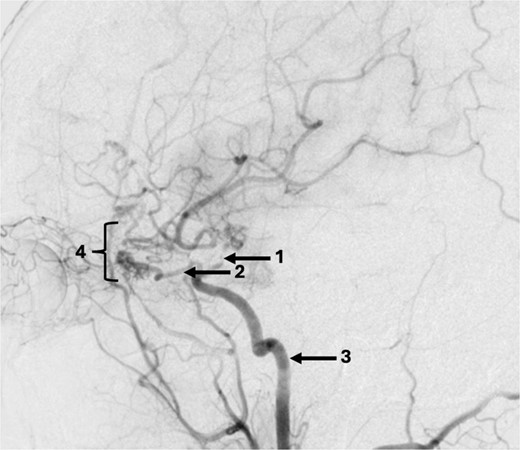

A 43-year-old lady, with known hypertension, presented with severe and sudden onset headache in 2010. Initial computed tomography (CT) head confirmed a diffuse subarachnoid haemorrhage (images not available) and a subsequent CT angiogram showed a right supraclinoid internal carotid artery (ICA) aneurysm (Fig. 1). CT Angiogram also showed an unruptured left posterior communicating which was thought not to be related to this patient’s presentation and managed conservatively with serial imaging. The patient underwent emergency craniotomy on the same day where an encircling Sundt clip was applied to secure the aneurysm. She made a full neurological recovery and was discharged from hospital. Post-operative day 1 CT angiogram demonstrated relatively normal calibre of the right A1 portion of anterior cerebral artery (ACA) and M1 portion of middle cerebral artery (MCA), in the terminal carotid region (Fig. 2).

Pre-operative CT angiogram demonstrates normal appearances of the (1) MCA, (2) ACA with, (3) laterally projecting terminal carotid sidewall aneurysm. (4) R ICA.